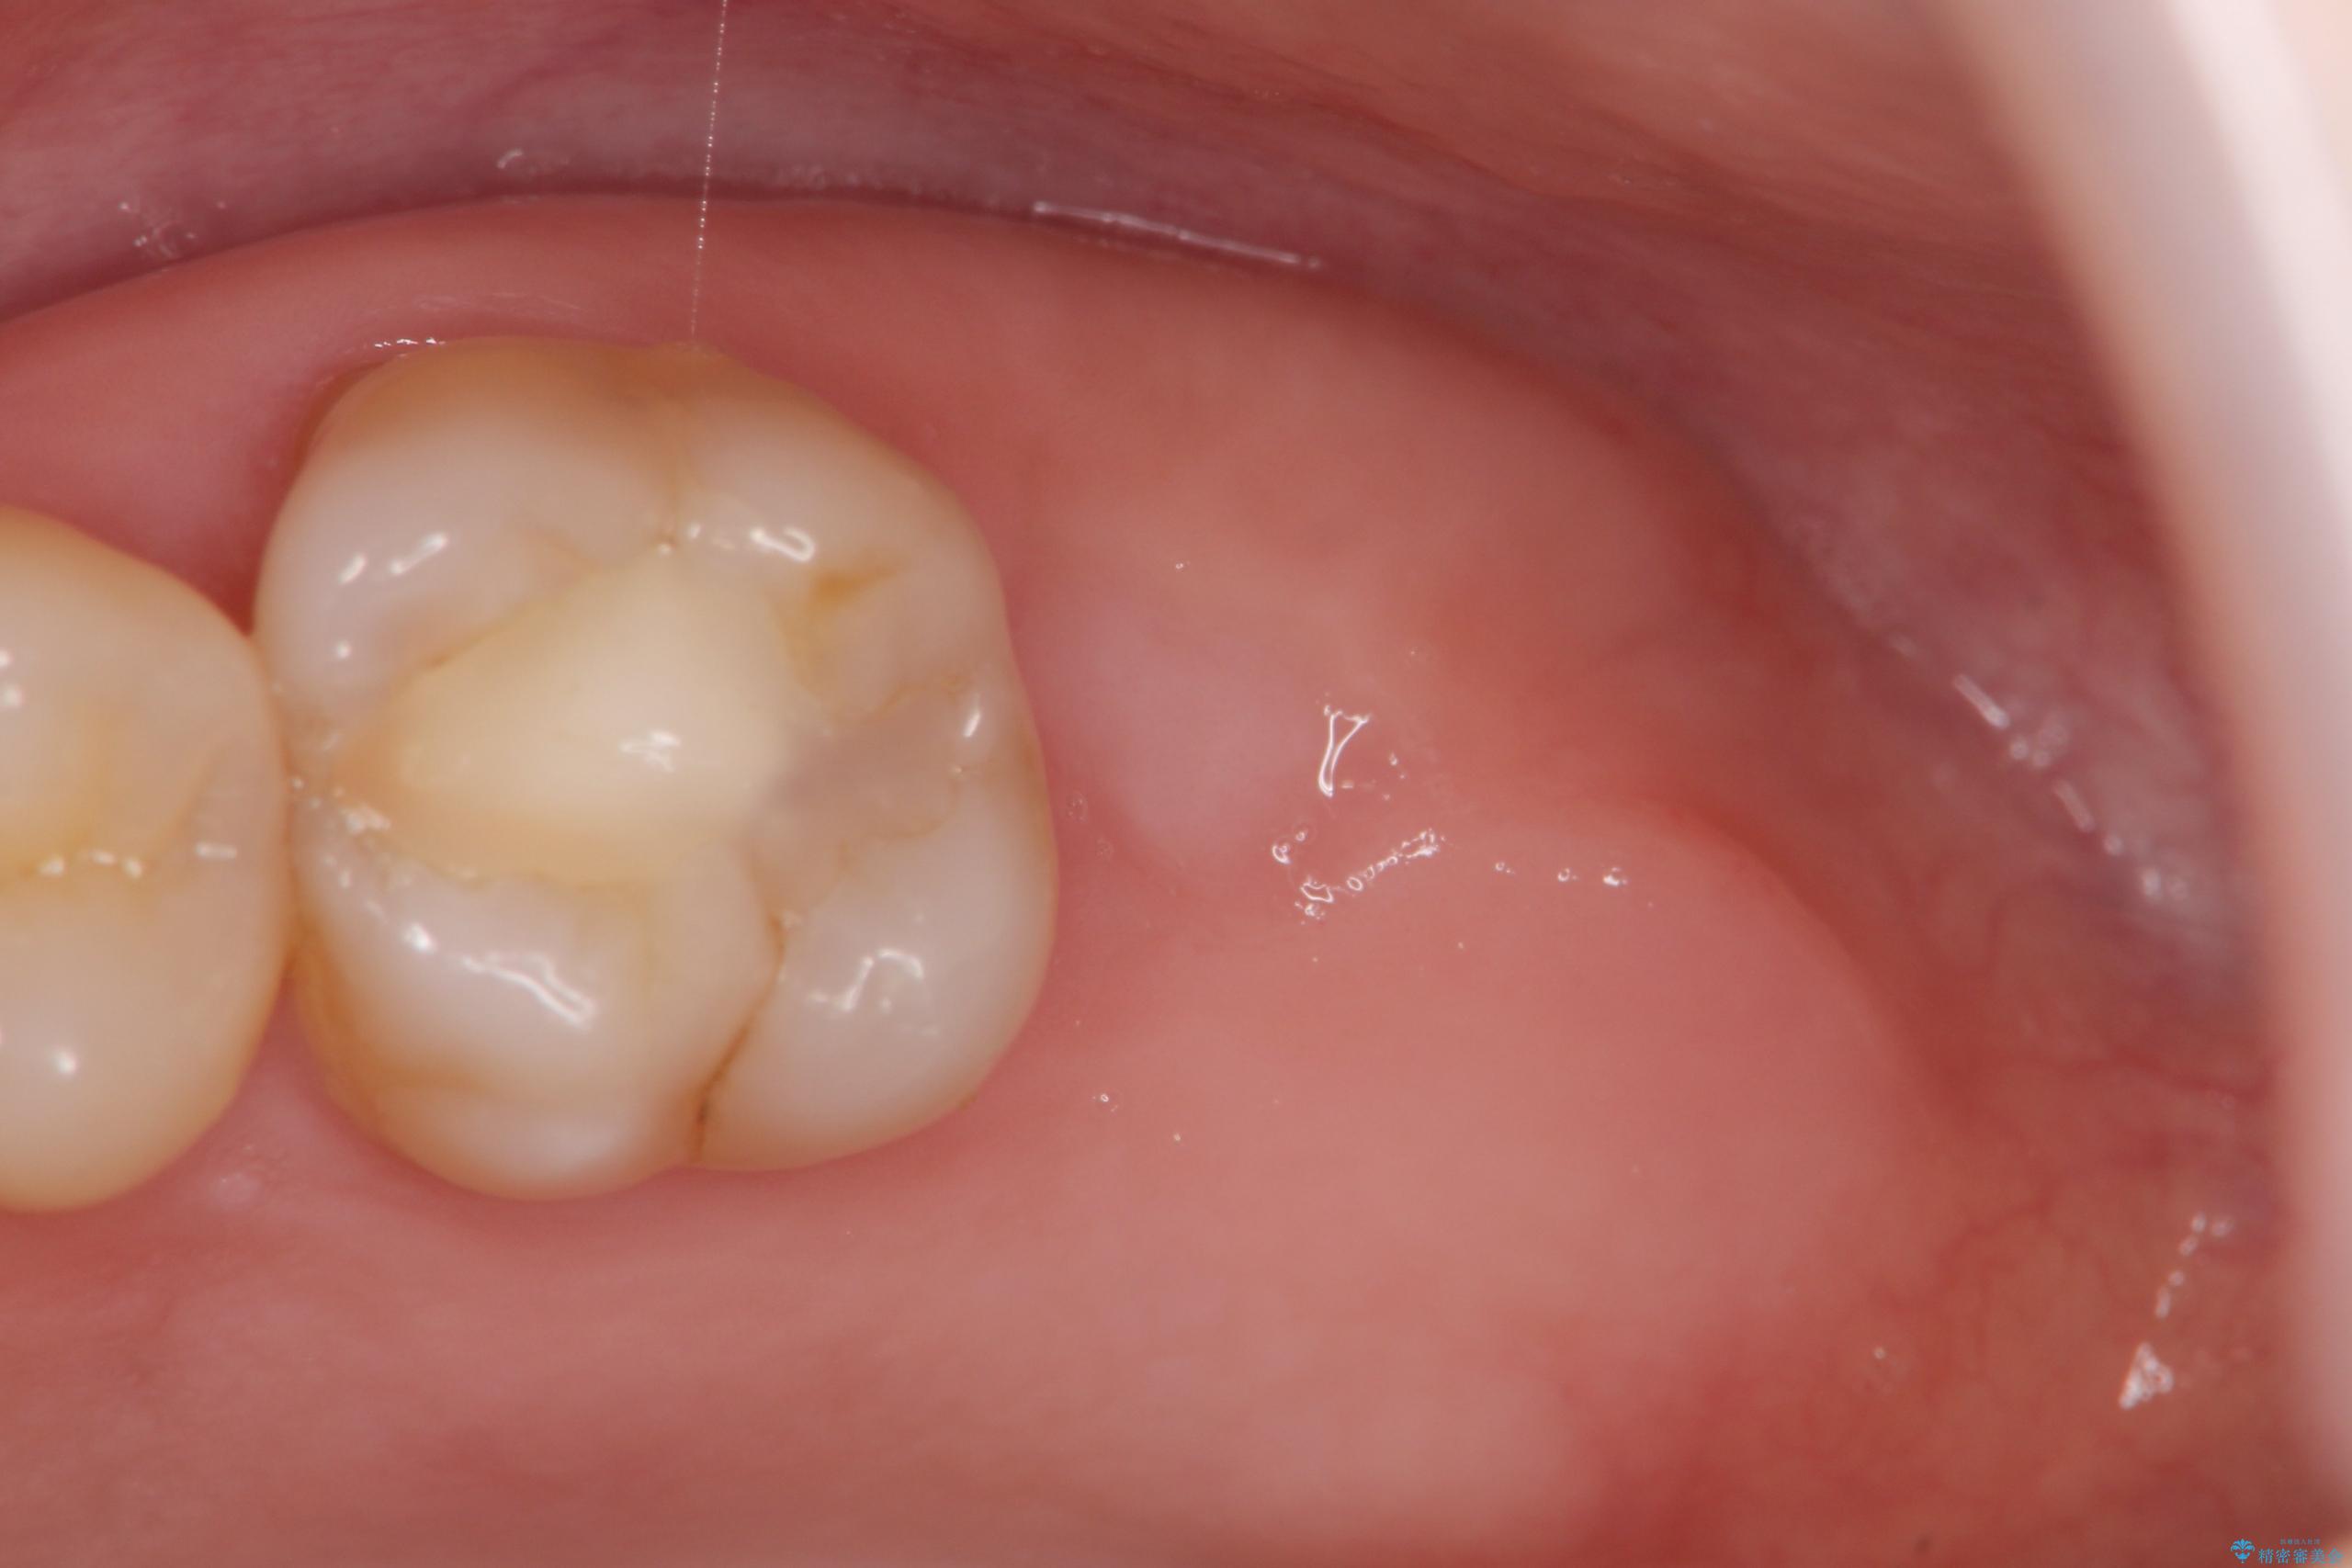

治療を終えて

歯の破折で抜歯を余儀なくされ、ショックが大きかったですが、しっかりとインプラントで咬合機能が回復することができ、喜んでいただくことができました。

治療後

【噛むと歯が疼く】歯牙破折からのインプラント治療 治療後画像 【噛むと歯が疼く】歯牙破折からのインプラント治療 治療後画像 【噛むと歯が疼く】歯牙破折からのインプラント治療 治療後画像 【噛むと歯が疼く】歯牙破折からのインプラント治療 治療後画像